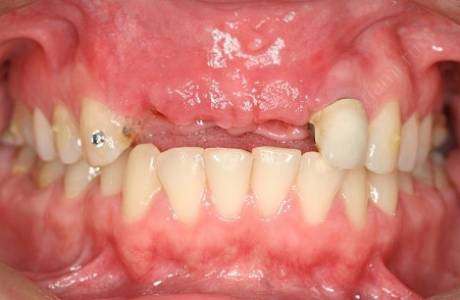

До лечения

Пациентка обратилась с жалобами на отсутствие жевательных зубов на нижней челюсти, неудовлетворительный внешний вид ранее изготовленных конструкции.

При остмотре также выявлено занижение высоты нижнего отдела лица и полное отсутствие прикуса, при том, что у пациентки изначально был патологический прикус с глубоким резцовым перекрытием.

Принято решение провести тотальную реабилитацию прикуса, восстановление эстетики и высоты нижнего отдела лица.

После лечения

На нижней челюсти установлены имланты. За время их приживления фронтальные зубы перелечены, восстановлены вкладками, на временных коронках зафиксирована нужная высота.

На все зубы были установлены коронки на основе диоксида циркония